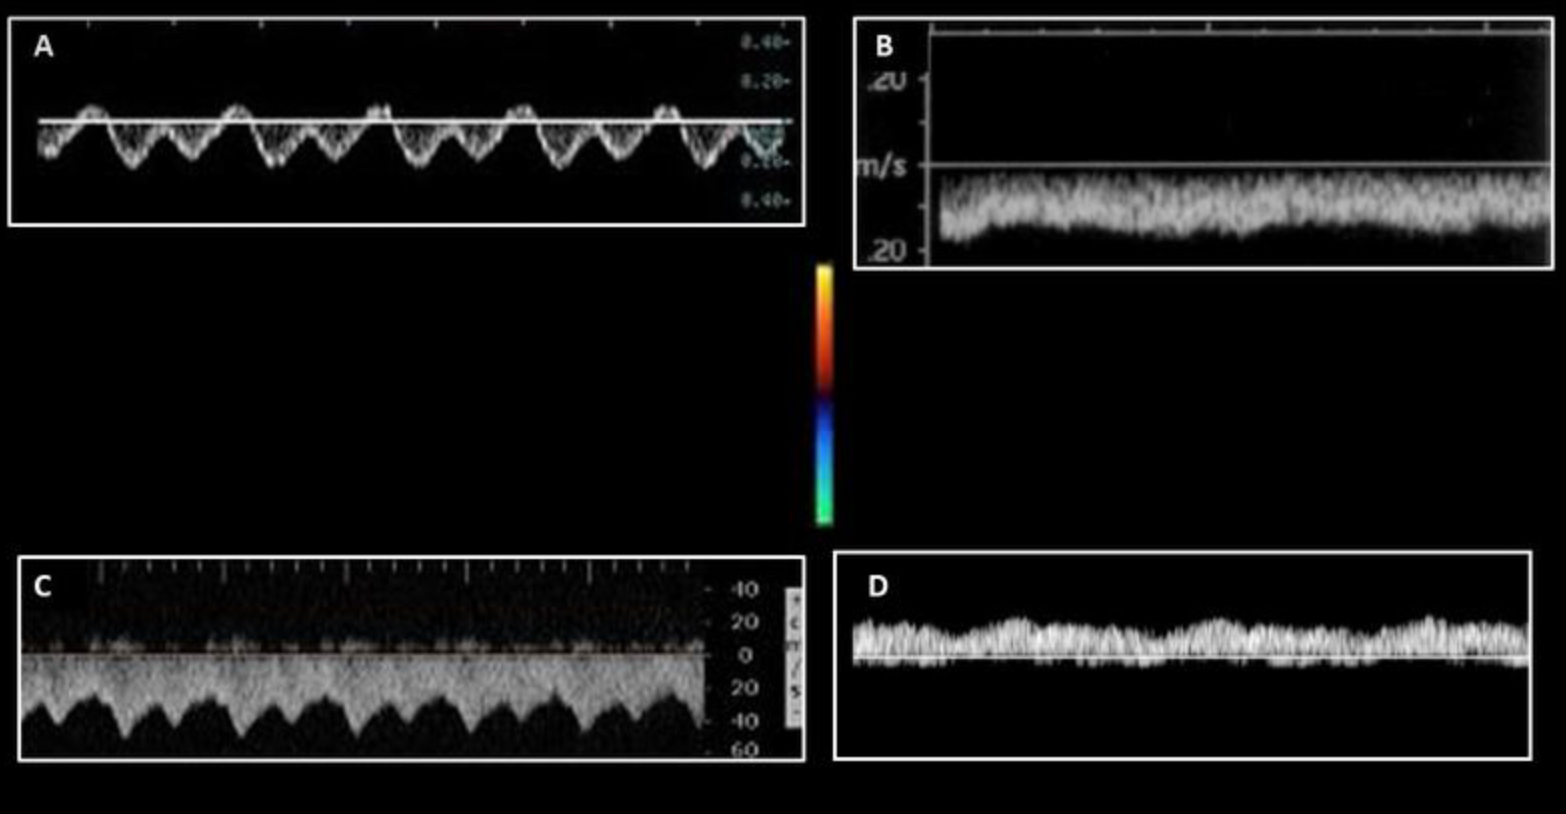

Which of the following terms can be used to describe a normal Doppler tracing from the hepatic veins?

Triphasic

What causes the hepatic vein flow to have a triphasic waveform?

Right atrial contraction and relaxation

Which of the following statements is true regarding the Doppler tracing displayed?

it could represent a Doppler tracing of normal flow in the right hepatic vein

Which waveform represents a normal inferior vena cava waveform?

A